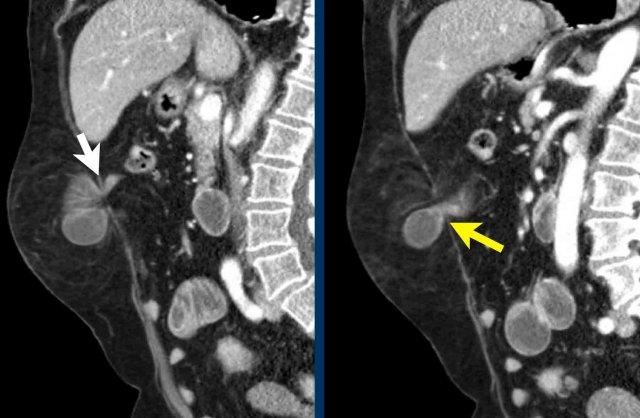

Đo kích thước trong trường hợp nhiều thoát vị

Bệnh nhân này có hai thoát vị.

Có một thoát vị đường giữa (đầu mũi tên màu vàng) và một thoát vị bên (đầu mũi tên màu trắng).

Trong trường hợp này, tổng chiều dài kết hợp và tổng chiều rộng được đo.